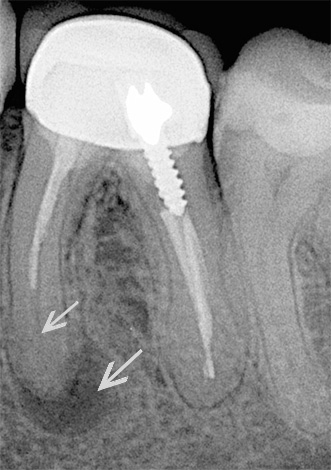

Um homem de 35 anos foi ao dentista com queixas de inchaço das gengivas na área do dente esquerdo por baixo, que periodicamente passa sozinho. Da história médica: o dente foi tratado anteriormente nos canais, a coroa de metal e cerâmica foi colocada há cerca de 2 anos. Os diagnósticos de inspeção visual, percussão, EDI e radiografias mostraram que o dente está localizado sob a coroa com o nervo removido e na região do ápice da raiz anterior 3,6 do granuloma do dente (canto inferior esquerdo, sexta consecutivo) é visível, o que representa uma área escura arredondada na imagem. O tecido circundante próximo à raiz posterior está dentro dos limites normais.

As causas da dor são bastante óbvias: na raiz anterior, o material de preenchimento passava apenas um pouco mais de 50% do canal, de modo que podemos assumir que durante a operação houve vários problemas associados à passagem do canal, sua expansão, lavagem e preenchimento, que posteriormente levaram à reprodução bactérias em uma área não lacrada.

A raiz posterior é selada quase no ápice, ou seja, não atinge o ápice radiológico visível de cerca de 1 mm. Portanto, não há nenhum problema sério.

Táticas de tratamento.Para eliminar fontes diretas de dor na forma de inflamação das raízes no topo, foi realizado um tratamento em fases:

- Dissecção com boro através da coroa;

- Abertura da boca do canal na raiz anterior problemática;

- Passagem e expansão do canal, não atingindo o ápice em 20-30%;

- Vedação com obturadores de núcleo mole no comprimento necessário;

- Ressecção (recorte) do topo da raiz anterior;

- Controle as imagens após o tratamento e após um ano;

- Coroas de substituição.